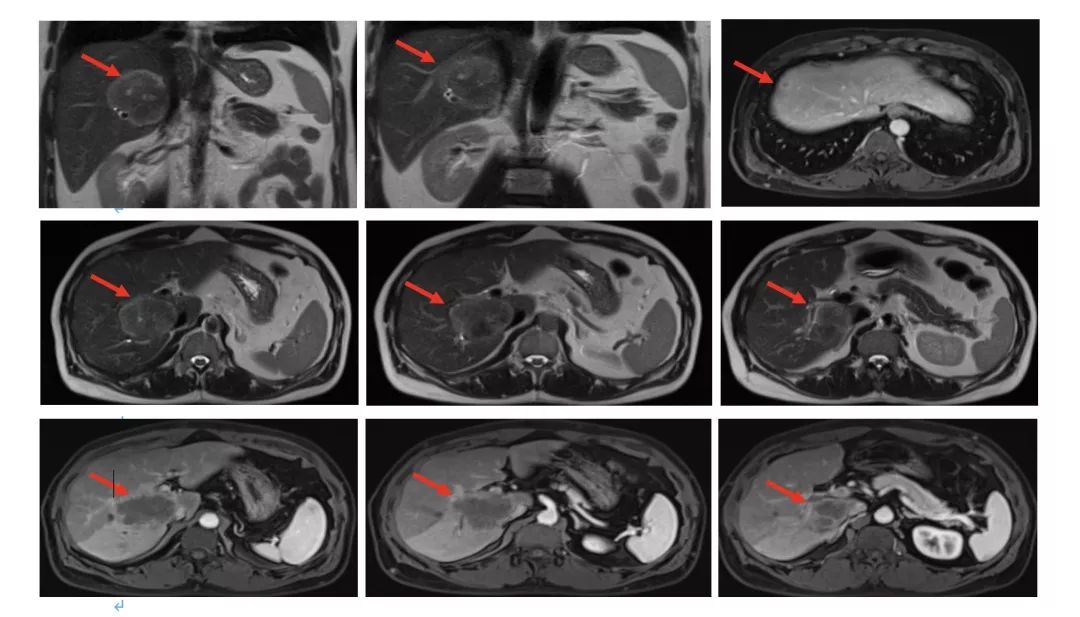

2017.6复查肝脏再次出现新病灶,右后叶包膜下边缘见2.2cm*1.4cm强化结节。

MDT讨论意见

-

肝脏病灶单发;

肝脏病灶争取局部治疗达到NED;

建议行肝脏转移灶手术治疗;

肝脏病灶手术治疗。

2017.6.6行腹腔粘连松解术+肝转移瘤切除术;

术后病理(肝右叶)绒毛管状腺癌,结合临床病史,符合结肠癌肝转移。

2017.7行肝转移灶术后瘤床放疗DT36Gy/6F;

2019.7.18复查MRI无异常。